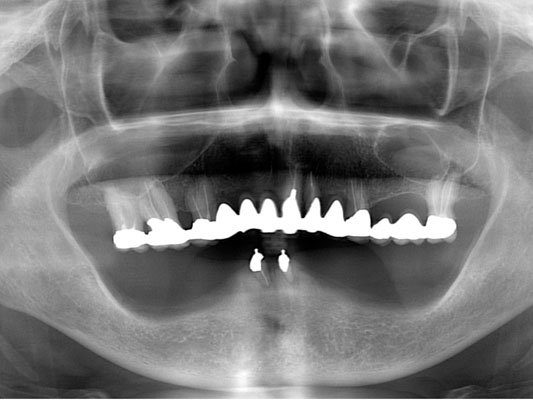

みなさんは歯を失ったら、元のように「噛めるようになりたい。」と考えられるのではないでしょうか。そして3つの選択肢のうち、ブリッジとインプラントは元の歯と同じように噛めますが、入れ歯は3割から5割の力でしか噛むことができませんので、多くの方がブリッジかインプラントのどちらにするかと悩み始めます。歯にダメージを与えないインプラントの方が良いに決まっていますが、「骨に金属のビスを打ち込む」ということに抵抗を感じる方も多いと思います。

しかし、ここで多くの方が見落としているポイントがあります。ブリッジや入れ歯を入れても、歯の根が増えるわけではないので、残っている歯の負担を軽減することはできません。これが、インプラントなら新たな支えとなるため、残っている歯の寿命を縮めることはなくなることです。

ここで確認しておきたいことがあります。当院で歯を抜く理由の2割が「虫歯」で、2割が「歯周病」です。残りの6割近い原因をご存知ですか?答えは、「破折」です。様々な理由で歯を割ってしまうのです。これは、意外と知られてないことです。そのため、歯に過剰な力がかかることに対する対策を全く考えていない方が多いのです。

言い換えれば、失った歯を補うときには、「虫歯リスク」や「歯周病リスク」にくらべ、全体の6割近いウェートで「力のコントロール」について考慮すべきなのです。(「力のコントロール」については別の記事で解説しますが、インプラントを入れる前、あるいは歯の治療をする前には必ず理解しておいて頂きたい内容ですので是非ご覧下さい。)

インプラントを入れようかと迷われている時、歯周病に似たインプラント周囲炎を危惧され、「歳を取ってからダメになるのじゃないか」、「介護されるころになったら磨けない」などとおっしゃる方が多いのですが、そういった方は、インプラントがダメになることばかりを考え、他の歯が割れてダメになることを考えられていないのです。

インプラントが不完全だからといって入れなければ、歯を失うリスクが高くなります。ペースメーカーと同じ理屈だと思うのですが、歯は何本もあるので危機感が薄いのではないのでしょうか。

インプラントを入れるには割り切って考えることが必要です。インプラントは完全なものではありません。天然歯に比べて多くのリスクを抱えています。しかし、たとえ10年しかインプラントが保たなかったとしても、その10年間はインプラントが噛む力を負担して、他の歯にかかる力を軽減し、歯の寿命を延ばしてくれたと評価することができれば、インプラントを入れた意味は十分にあると思います。